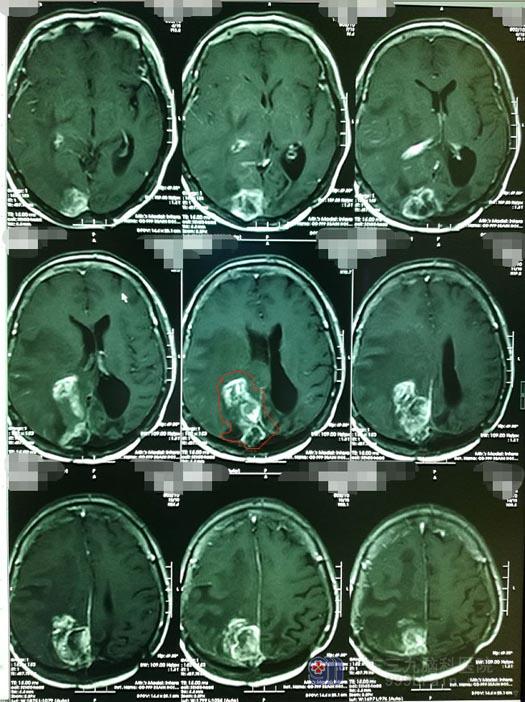

脑部影像检查提示:右侧枕顶部镰旁占位性病变,大小约43mm×33mm×52mm,病灶与右侧侧脑室内脉络丛关系密切,灶周水肿波及右侧额颞枕顶叶、右侧基底节区及胼胝体压部。

“从影像上看,肿瘤非常大,而且具备了恶性肿瘤的生长习性,部分肿瘤已经长入到上矢状窦内,整个右侧大脑半球水肿非常厉害,患者已经接近失明、偏瘫,如果再不把这个肿瘤拿下,对患者而言,她可能没有下一次手术的机会了。此次手术中需要处理好肿瘤与上矢状窦、脑膜及各种血管间的关系,才能尽可能的避免肿瘤复发再生长。现在,手术是唯一的选择。”鲁明了解病史及查看影像资料后坦诚地告诉钟女士的老公。